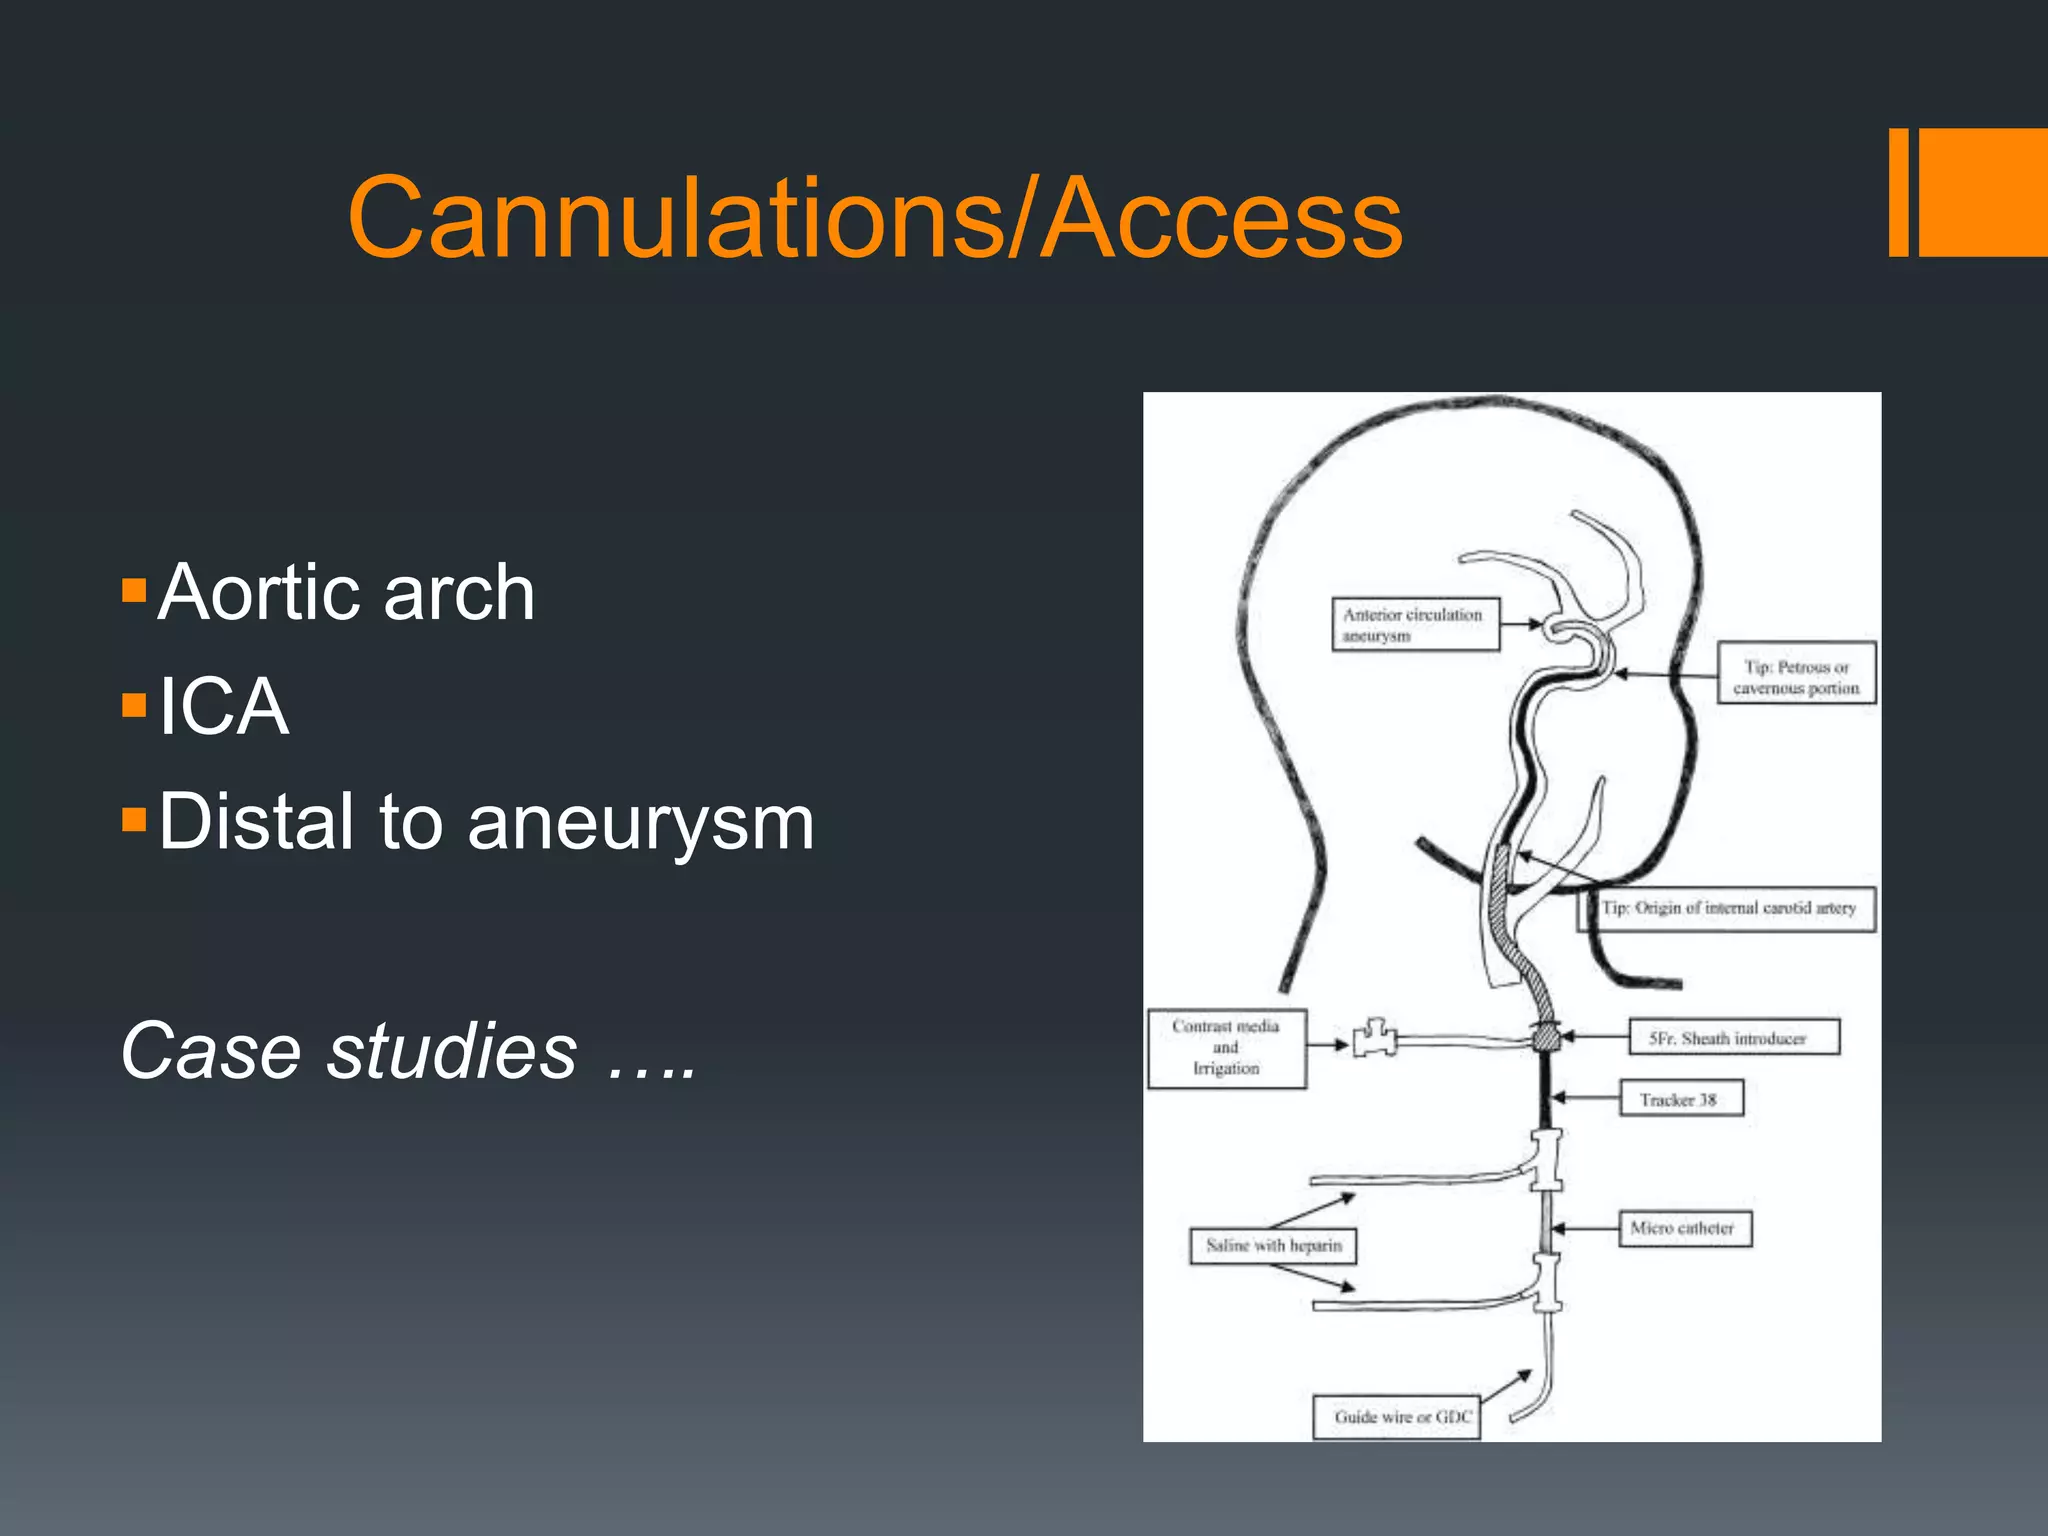

This document discusses tricks and techniques for difficult cannulations during neurointerventional procedures. It outlines strategies for accessing the aortic arch, internal carotid artery (ICA), and areas distal to aneurysms. Long sheaths, distal access catheters, and co-axial techniques are presented as options that have improved cannulation success. Guidance on sheath and catheter selection is provided for different vessel paths. The importance of catheter placement as high as possible in the ICA is emphasized. Reverse curve cannulations are also mentioned. Overall, the document stresses that careful cannulation is critical for procedural success and different strategies may be needed depending on the vessel target.